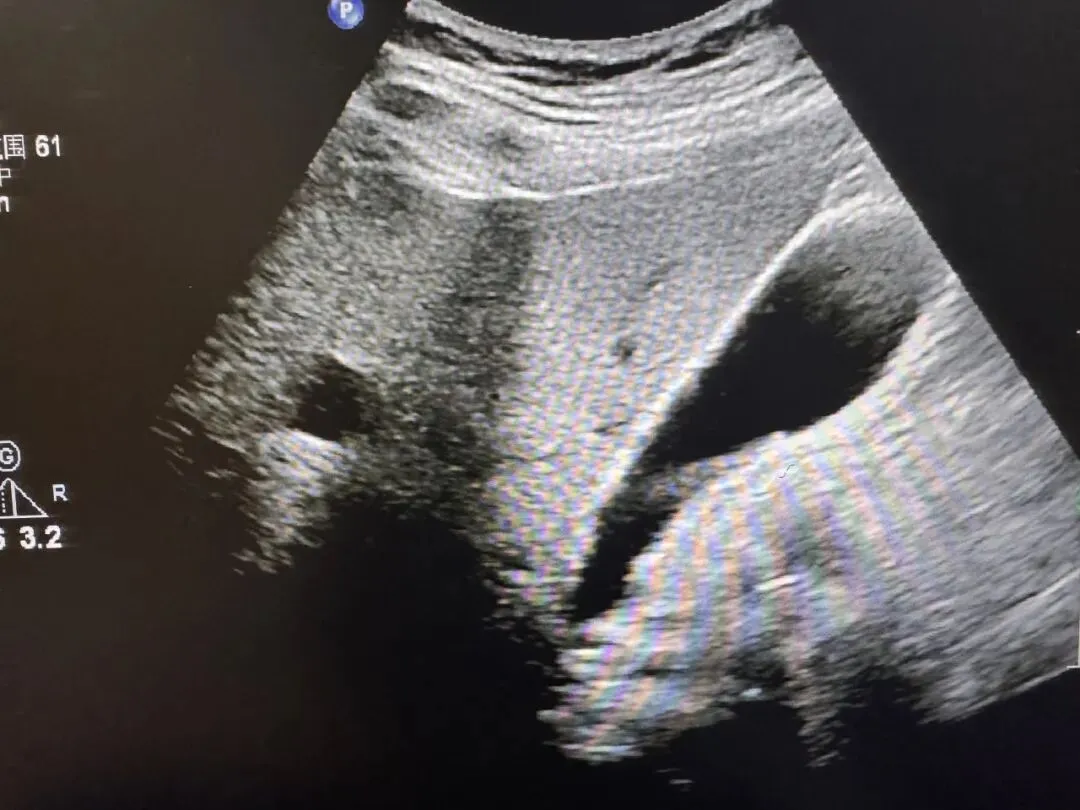

胆囊腺肌症

增厚胆囊壁并其内小液性暗区